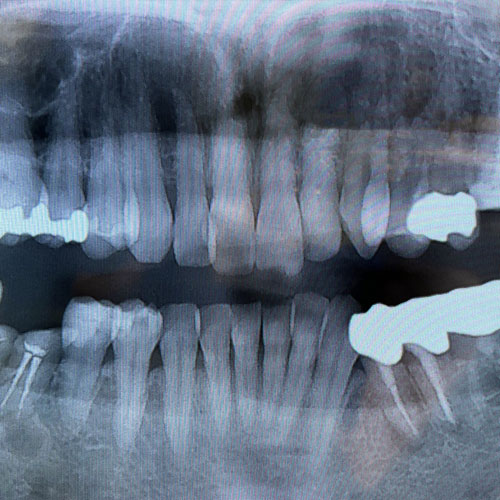

A

病巣除去のための治療

レントゲンに写った歯の根っこにある病巣や歯周疾患を診断して、総合的な判断のもと治療計画を立て、経過を見ながら治療を行います。具体的な方法として抜歯や扁桃摘出(耳鼻科との連携による)なども検討されます。